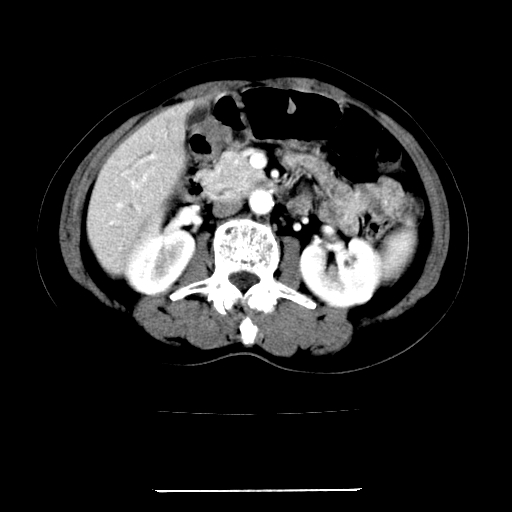

标题: CT22301:女,67岁,上腹部疼痛一周伴皮肤黄染,无发热。 [打印本页]

女,67岁,上腹部疼痛一周伴皮肤黄染,无发热。

考虑:肝内胆管结石继发肝内胆管扩张,右肾旋转不良。

考虑肝胆管癌;胰头占位?【形态失常,体积增大】

1、肝门高密度影下层面和胰头层面可见轻度胆管扩张,而静脉和延迟期均未见扫描完胰头,不能完全排除胰头占位。2、肝门部高密度影,考虑钙化或结石。